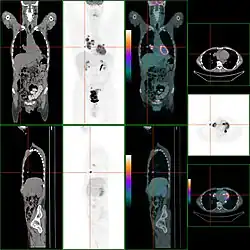

Knochenmetastasen

Knochenmetastasen unterschiedlicher Tumorerkrankungen können mit PET/CT sehr gut nachgewiesen werden. Das Verfahren ist sensitiver als die SPECT und erheblich sensitiver als die planare Skelettszintigrafie, jedoch auch aufwändiger und somit teurer. Je nach Tumorentität werden unterschiedliche Tracer verwendet, meist jedoch FDG und Natriumfluorid, beim Prostatakrebs auch 11C- oder 18F-Cholin. Metabolische Aktivität des Tumors ist mit Hilfe des Tracers FDG, die Reaktion des Knochens auf den Tumor mit der Natriumfluorid-PET/CT meist gut darstellbar (siehe Bildbeispiele).[33]

-

HDP-Skelettszintigramm eines Patienten mit Nierenkrebs: Die Knochenmetastasen im Halswirbelkörper 7 und in der Lendenwirbelsäule (LWK 1&2) sind aufgrund der geringen Auflösung der planaren Skelettszintigrafie nur zu erahnen. -

SPECT-Aufnahme des HDP Skelettszintigramms desselben Patienten; von den beiden Metastasen in der Lendenwirbelsäule ist nur eine einzige Läsion erkennbar; die Läsion in der Halswirbelsäule ist nicht dargestellt. -

FDG-PET desselben Patienten: Die osteolytische Knochenmetastase im Halswirbelkörper reichert FDG nicht an und ist nur im CT erkennbar. Die beiden weiteren Knochenmetastasen in der Lendenwirbelsäule werden dagegen auch in der FDG-PET/CT dargestellt. -

Natriumfluorid-PET/CT desselben Patienten: Die osteolytische Knochenmetastase in der Halswirbelsäule zeigt einen extremen Uptake und ist klar erkennbar. Die beiden weiteren Knochenmetastasen in der Lendenwirbelsäule stellen sich in der PET/CT-Aufnahme ebenfalls sehr gut dar. -

Vergleich derselben Läsion des vorgenannten Patienten: Die FDG-PET/CT-Aufnahme zeigt die Stoffwechselaktivität des Tumors. -

Vergleich ein und derselben Läsion des vorgenannten Patienten: Die Natriumfluorid-PET/CT-Aufnahme zeigt die Stoffwechselaktivität des Knochens als Reaktion auf den Tumor.

Eine falsch positive, diffuse FDG-Aufnahme kann im Knochenmark als Reaktion auf eine kurz zuvor erfolgte Chemotherapie beobachtet werden. Bei der PET-Bildgebung mit Natriumfluorid (NaF) ist zu beachten, dass auch nach einer erfolgreichen Therapie im Knochen eine Anreicherung zu beobachten sein kann, die in diesem Fall nicht die Aktivität des Tumors, sondern die Reparaturaktivität der Osteoblasten (knochenbildenden Zellen) darstellt.[33]